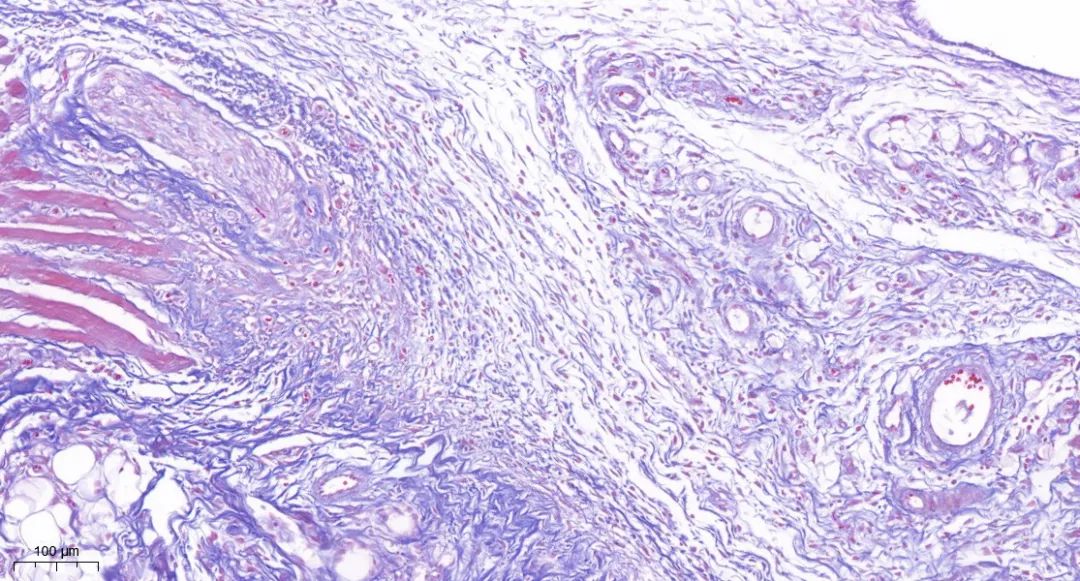

Masson染色

Masson染色,也称为马松染色,是一种广泛应用于观察组织纤维化的经典结缔组织染色方法。它通过特殊的染色步骤和染色剂,能够清晰地区分并显示组织中的胶原纤维和肌纤维,为研究人员提供了深入了解细胞和组织结构、形态及变化的重要工具。

其中,胶原纤维通常呈现为蓝色,而肌纤维则呈现为红色。

※实验结果示例:

胶原纤维通常呈现为蓝色,而肌纤维则呈现为红色。

masson染色·皮